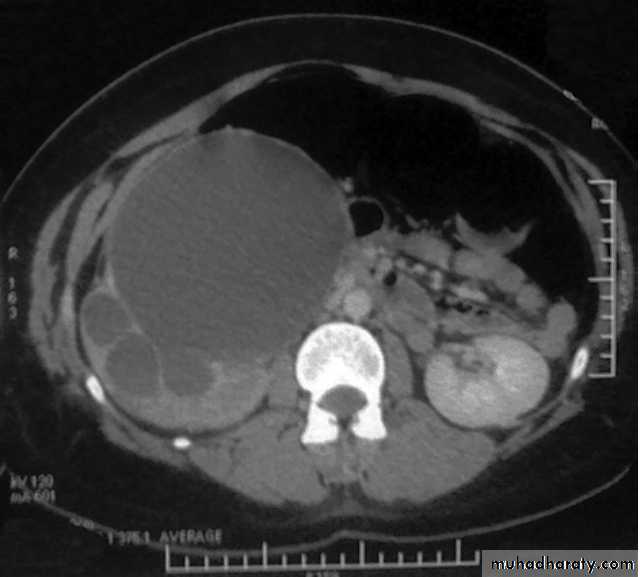

Ct enhanced

Renal cyst type 4 with calcification and peripheral enhancement needs radical nephrectomyBosniak's class II renal cysts. A, CT scan shows right renal cyst with thin internal septation.